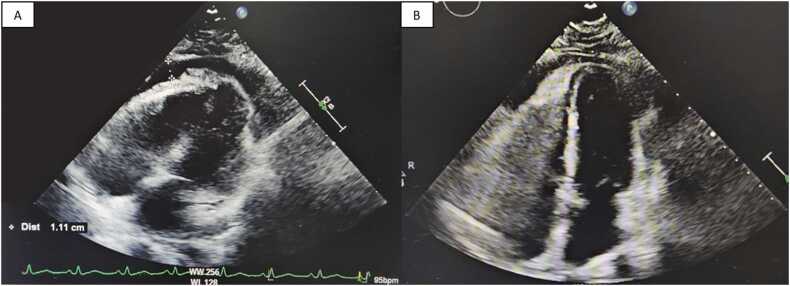

Influenza A viral infection classically presents as pulmonary manifestations which often require symptomatic management. It can rarely be complicated by pericarditis with concurrent pericardial effusion. We present a unique case of myopericarditis with a pericardial effusion caused by Influenza A. Our patient was presented with elevated troponin and BNP. Chest x-ray showed an enlargement of the cardiac silhouette and clear lungs. CT angiography was remarkable for pericardial effusion. An echocardiogram was performed which demonstrated mild concentric left ventricular hypertrophy with small to moderate circumferential pericardial effusion, and no echocardiographic signs of cardiac tamponade. The significance of our case makes clinicians aware that acute myopericarditis with concurrent pericardial effusion can lead to fatal complications such as cardiac tamponade or cardiogenic shock if left untreated. Early diagnosis and treatment as presented in our case could reduce the risk of such severe cardiac events from occurring.